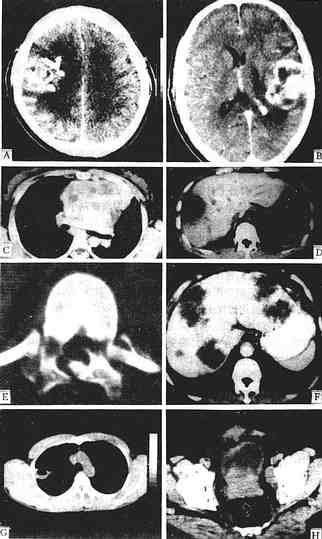

CT诊断应用于各系统疾病有以下特点及优势,参考图1-2-6。

图1-2-6 CT图像

少支胶质细胞瘤增强,右额、顶叶有一较大不规则肿块,强化不均,周围有低密度水肿区

星形细胞瘤 增强,左额顶叶有一不均匀强化肿块,不规则,内有未有强化的低密度区,周围有低密度水肿区,中线结构右移

胸腺增生 平扫,胸腺区有一分叶状密度均一病灶,仍呈胸腺状,主动脉受压右移

肝脓肿 平扫,肝右叶有一低密度灶类圆形,中心部密度更低为脓腔,周边为脓肿壁呈“双边征”

肝转移癌 增强,肝左、右叶多个大小不一、不规则低密度灶,周边有细的强化环围绕

肺脓肿 平扫,右上叶有一空洞性病灶,内壁光滑,并见气液平面,胸部X线片曾疑肺癌